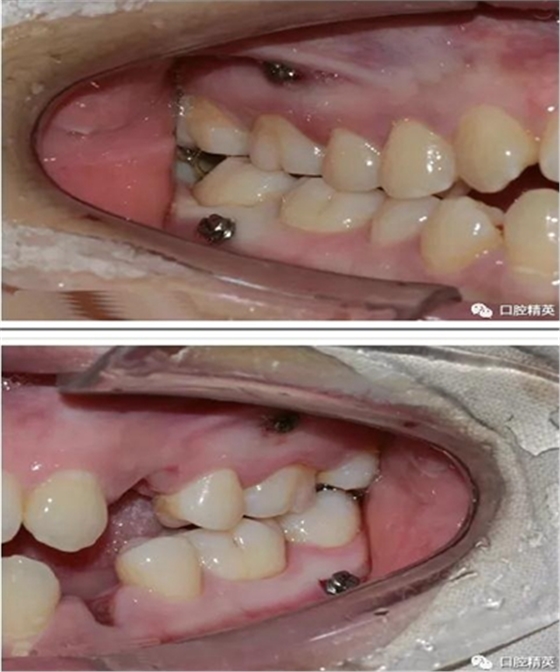

一般情況下是成年人使用,特殊病例十三、四歲的小孩可以用。種植釘可以打在牙槽骨的任何部位。可以在2個(gè)牙齒之間的牙槽骨上打釘,或者打在頰側(cè)牙槽骨與牙根之間,主要看你是如何應(yīng)用支抗了。2個(gè)牙齒之間的牙槽骨上打釘,支抗作用拉動的牙齒有限,而打在頰側(cè)牙槽骨與牙根之間可以將整個(gè)牙列拉向遠(yuǎn)中移動。種植支抗釘在矯正結(jié)束后要拿下來。

1、上頜種植釘常見位置在5,6之間;下頜種植釘常見位置在6,7之間。

2、助攻型種植釘,上頜與頜骨成30-40°角,下頜與頜骨成10-20°角(目的:1、降低損傷牙根及牙周膜的機(jī)率;2、使種植釘盡量植入骨皮質(zhì)內(nèi),降低松動機(jī)率);自攻型種植釘與頜骨垂直;個(gè)人習(xí)慣:自攻型種植釘上下頜均與頜骨成30-40°角。